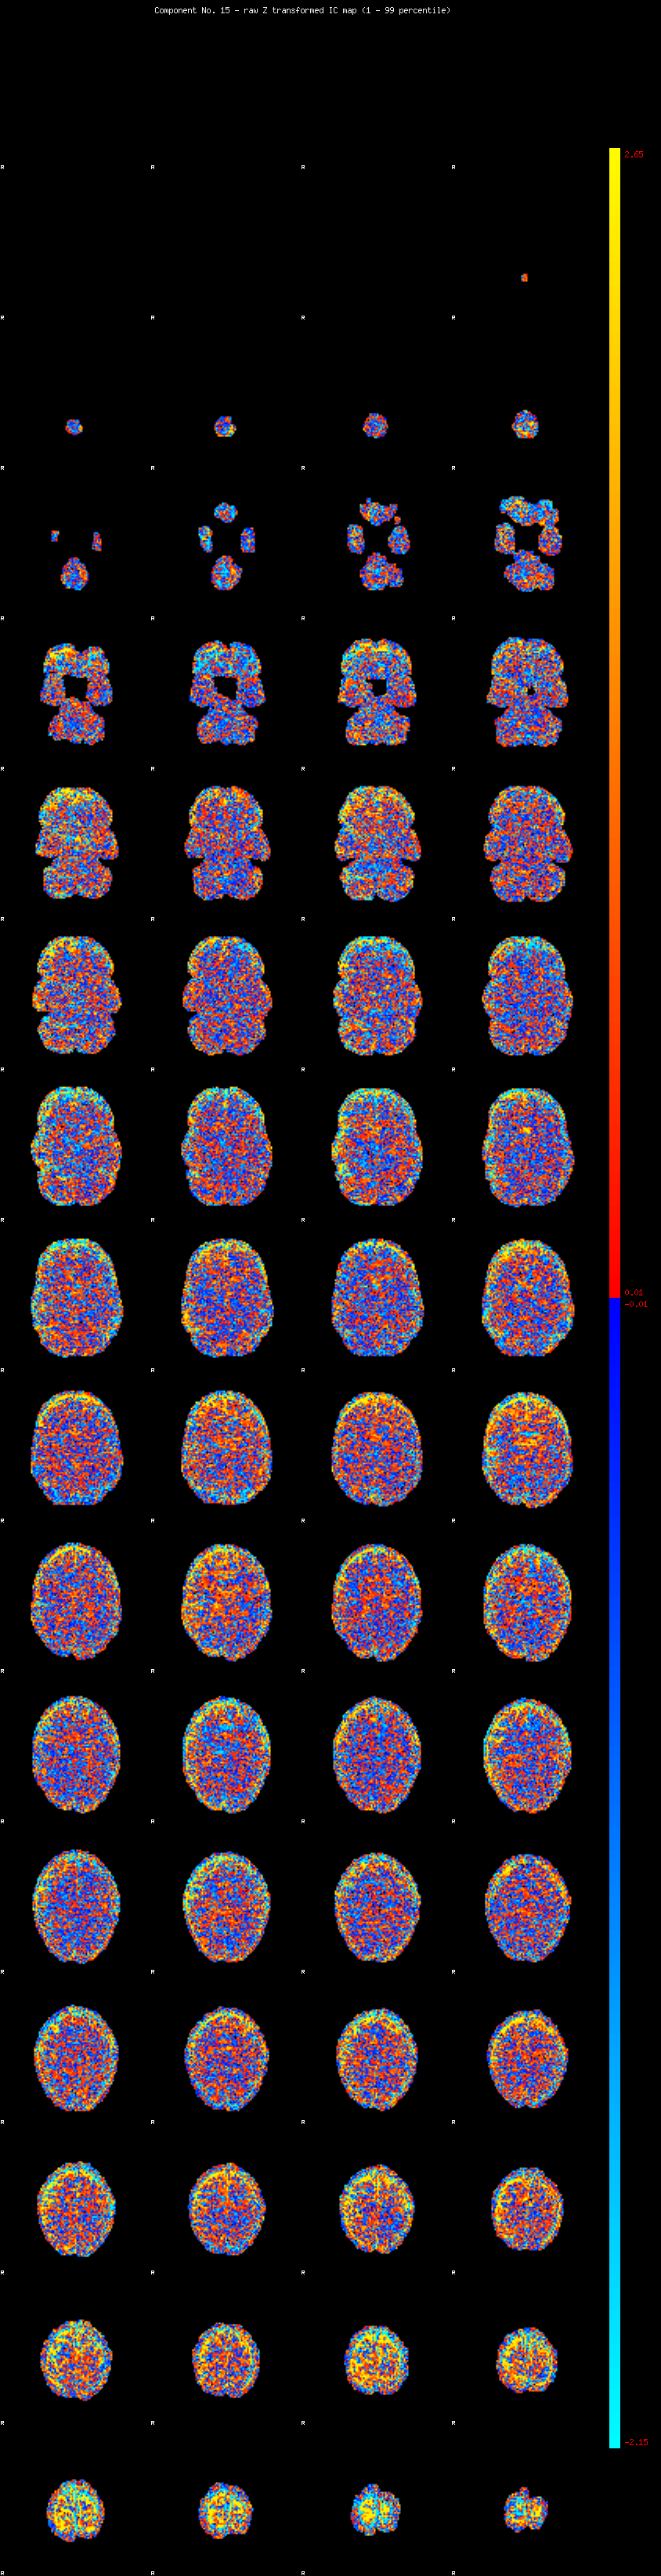

IC_15 Mixture Model fit

Means : 0.000000 2.705384 -2.443181

Vars : 1.000000 2.505798 1.790712

Prop. : 0.859121 0.087894 0.052985